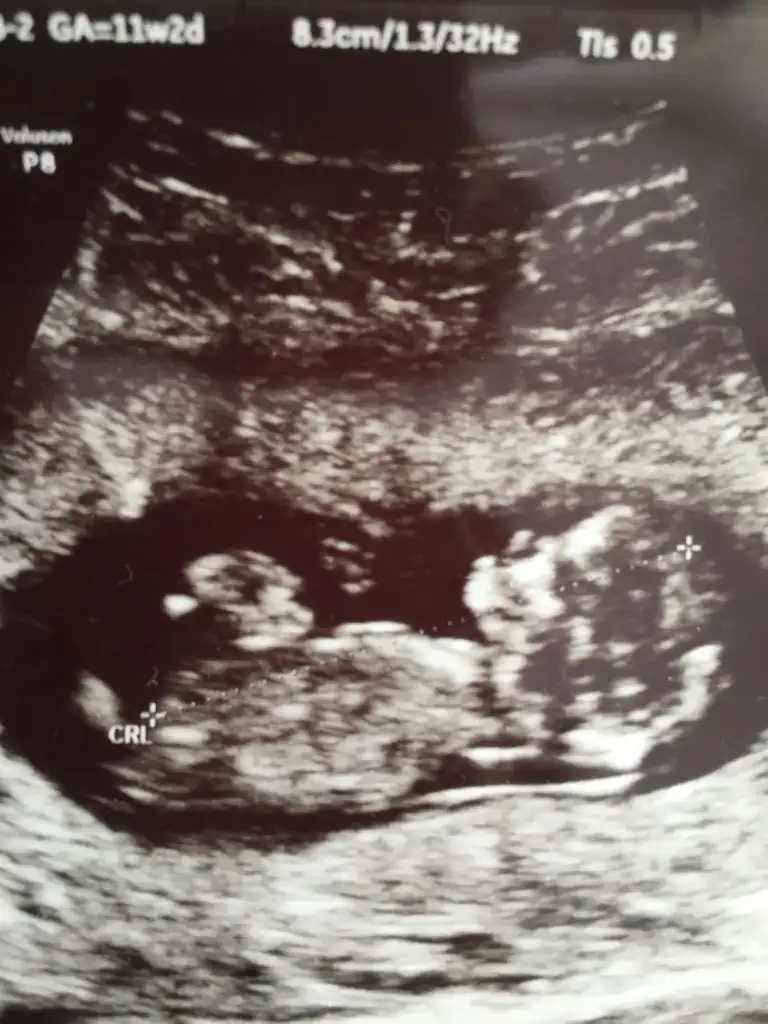

Merhaba bana da bi tahminde bulunur musunuz çok merak ediyorum🥰

11+2 haftası

• 613E1E18-2B48-40B4-A8D5-57B08FFF203B.webp

613E1E18-2B48-40B4-A8D5-57B08FFF203B.webp

26,5 KB · Görüntüleme: 58

• 0D24E19C-62C1-483B-BC67-BF84BDD42234.webp

0D24E19C-62C1-483B-BC67-BF84BDD42234.webp

34,9 KB · Görüntüleme: 43

• DE337620-2C05-4EA4-A505-D7EE0A7947DA.webp

DE337620-2C05-4EA4-A505-D7EE0A7947DA.webp

34,5 KB · Görüntüleme: 50

Canım bi de bu var ,ben de bugün başka doktora gittim direkt erkek dedi emin mısınız dedim sanki pipi gördüm dedi ama bir ay sonra netlesir dedi :)

Kız tabiki burda ama sonraki büyük haftada nub olmaz ☺️ demekki kordon gelmiş yoksa diğeri net bariz kız nubu 🙈